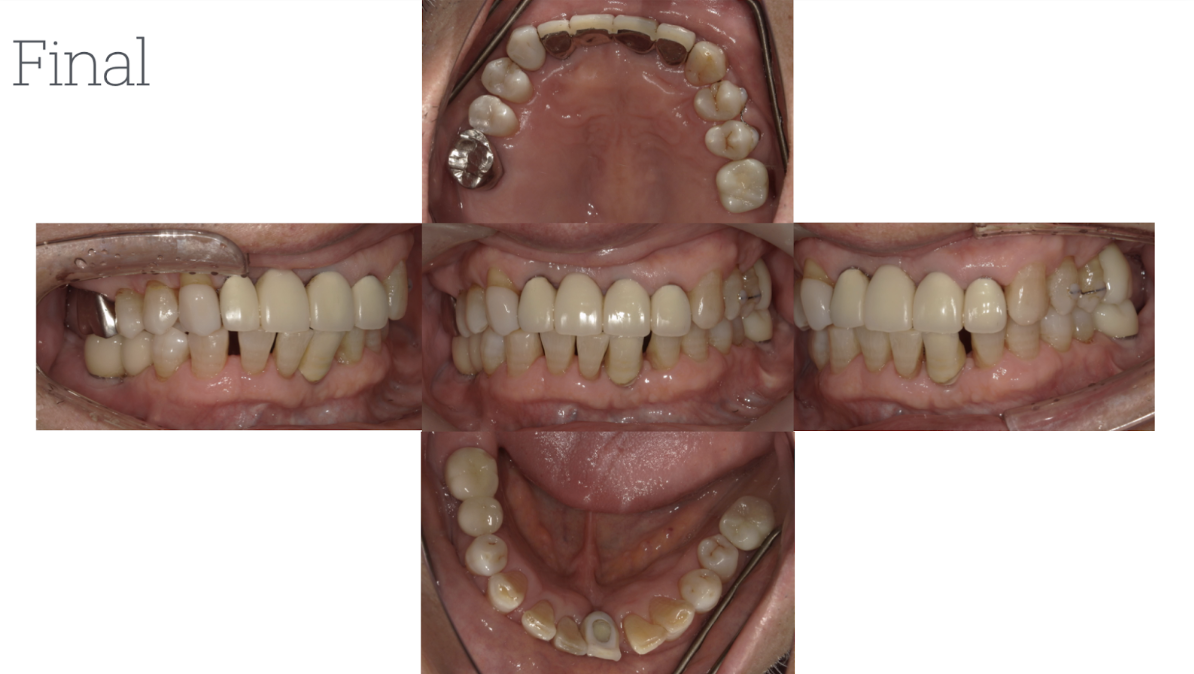

患者2

年齢性別:60代女性

主訴:右上被せ物の脱離にて来院。噛み合わせが深く、前歯を突き上げるような状態になっているため今回被せ物が維持できなくなったため矯正治療を行い、噛み合わせの改善を図った。矯正治療後、インプラント埋入を行い全体的な噛み合わせの調整を行った。

治療後、メインテナンスを継続中。